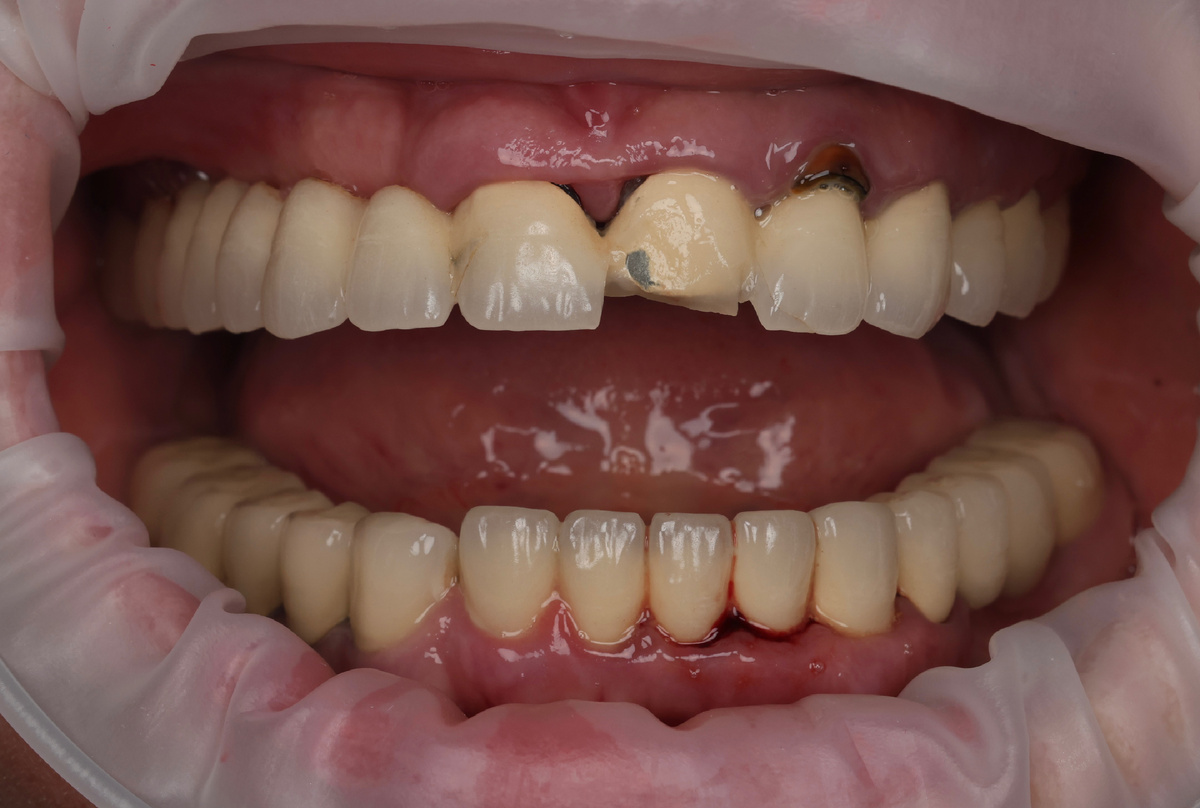

Если вы посмотрите на фото "до", то вряд ли подумаете, что нам пришлось удалить все зубы на верхней челюсти...

Однако, вся верхняя челюсть состоит из сплошной подковы из металлокерамики. Это, само по себе, допустимо, но не всегда и не везде. Снизу тоже МК, но не подкова.

Пациентка пришла с жалобами на боль, неприятный запах, скол керамики. Она уже понимала, что её ожидает впереди.

Первое, что бросилось в глаза - конструкция на верхней челюсти справа. Мост от первого резца до седьмого зуба - 5 единиц без опоры в виде корней, имплантатов:

Внимание - пять единиц подряд висят в воздухе! Зубы 1.2, 1.3, 1.4, 1.5, 1.6 - это просто керамические болванки без опоры на корни. Мост через пропасть, не иначе.

Зуб 1.1 - скол керамики до металла.

Зуб 2.2 - перелом корня. Причём настолько явный, что часть его торчит из десны: